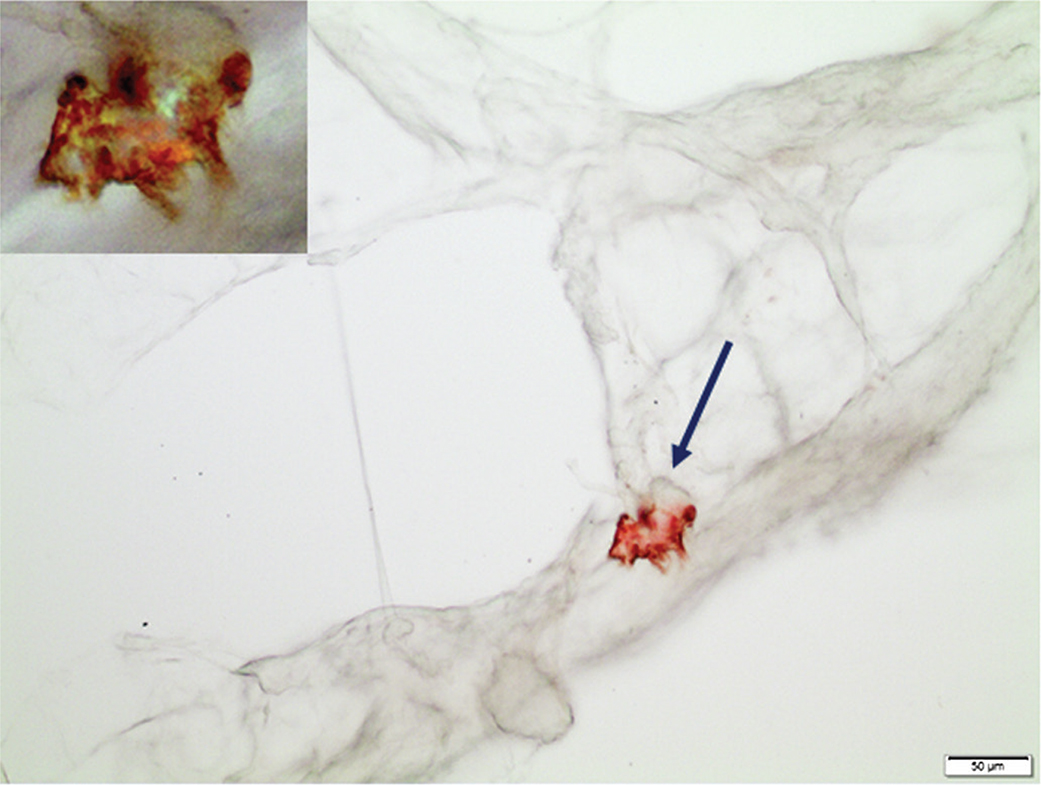

We have developed a unique principle way to diagnose systemic amyloidosis based on fat tissue biopsies, and the results for the three-year period (2018-2020) are shown in Table 2. About one-third of them (440) contained amyloid. The amount of amyloid varied, ranging from a situation with almost no normal tissue structures remaining to very tiny deposits. Western blot analysis revealed the fibril protein in 72.5% of the cases. Nineteen further biopsies were rich in amyloid but not possible to type with our antibodies. The remaining 102 biopsies contained small amounts of amyloid, often only as one or a few but distinct deposits. For further characterization of these materials, we applied IHC and used the original squeeze-prepared slides. Since the deposits often were minimal and could be difficult to find again (Figure 1), their coordinates in the microscope were noted before removing the cover glass. The slide was then taken back to water before IHC was performed in the usual way. In this way, it was possible to identify ATTR as the amyloid fibril protein in 51 cases (Figure 3). In 51 other cases which were highly suspected to be of ATTR nature, this method did not give a convincing result due to the minimal amount of amyloid, often only one dot-like deposit, a common finding in ATTR amyloidosis.

Figure 3. A sharply delined amyloid particle in a subcutaneous fat tissue biopsy. The amount of amyloid (arrow) was too sparse to analyze by western blot. Therefore, the Congo red stained squeeze preparation was subjected to IHC with our anti-ATTR antibody 7X, resulting in evident labeling of the deposit. Insert: the same particle at higher magnification, visualized in polarized light. Green-red-yellow birefringence due to the remaining Congo red staining is obvious. Immunolabeling was shown with 3,3’-diaminobenzidine. Bar = 50μm.